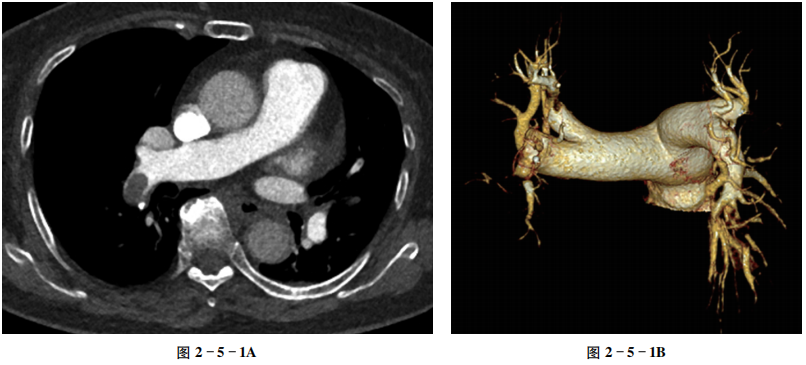

右肺动脉下支管腔内椭圆形充盈缺损影,周围环绕高密度对比剂(图2-5-1A);容积再现图像示右肺动脉充盈缺损(图2-5-1B)。

【重要征象】

肺动脉腔内充盈缺损。